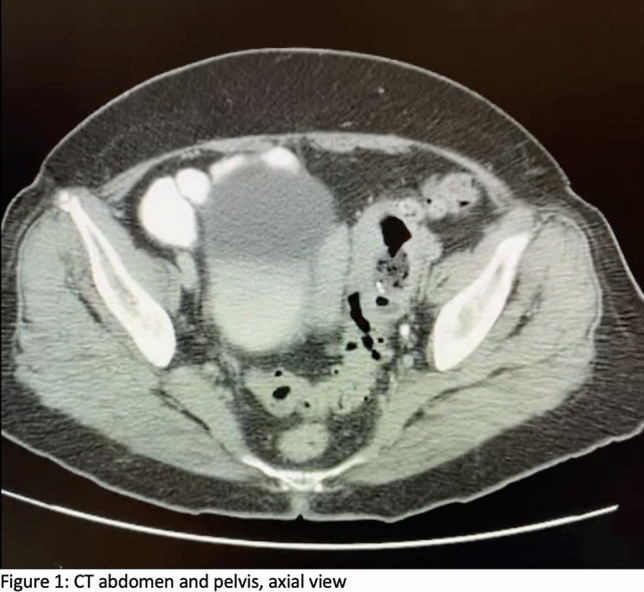

Methods and Procedures: Twenty-four patients underwent abdominal wall reconstruction (AWR) between January 2017 and June 2022 by a single surgeon at our institution. Lifestyle information (smoking, diabetes, and obesity status) and procedure-related metrics (pre-operative botox use, hernia characteristics, and mesh type) were obtained. The ellipsoid formula (V = 4/3ABC) was used to calculate volume of the hernia sac (VIH) and abdominal cavity (VAC) (Fig. 1). Measurements at initial visit and time of surgery were compared and analyzed using a two-tailed T Test (p < 0.05 signified significance).

Fig. 1 Hernia sac measurements for calculating VIH (Left to right: axial, sagittal, coronal)